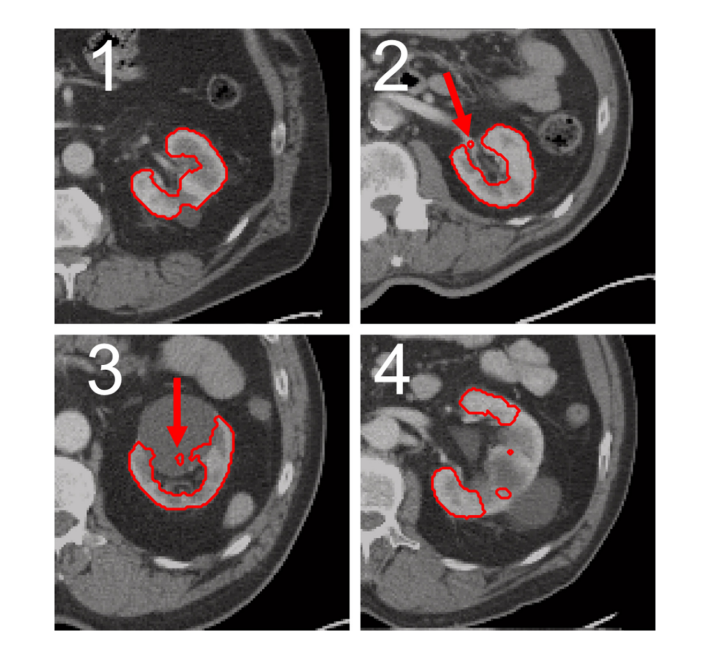

Figure 3 presents an exemplary depiction of automatically generated segmentation results for four scoring values. All segmentations were meticulously developed using only CT scans and method A1. The segmentation shown in Figure 3a, which received a rating of 1 (upper left, image A), exhibits no discernible inaccuracies. In Figure 3b, located at the top right (image B), an incorrect portion of the renal hilus was segmented (highlighted by a red arrow), leading to an assessment score of 2. Figure 3c, positioned at the bottom left (image C), includes parts of a cyst within its segmentation area (indicated by a red arrow) and was awarded a score of 3. Finally, Figure 4c, located at the lower right corner (image D) and given an assessment score of 4, reveals noticeable inaccuracies due to incomplete kidney segmentation as indicated by red arrows.

图 3展示了四种评分值自动生成分割的典型实例。所有分割均基于方法A1生成。对于评分为1的情况(位于左上角的图像1),未能识别出任何错误。右上方肾脏区域有一小部分未正确分离(由红色箭头标注),因此评分为2。左下角(图像3)展示了囊肿部分被包含在内的情况,因此评分为3。右下角对应的图像4显示了整体分离效果较为简单的情形